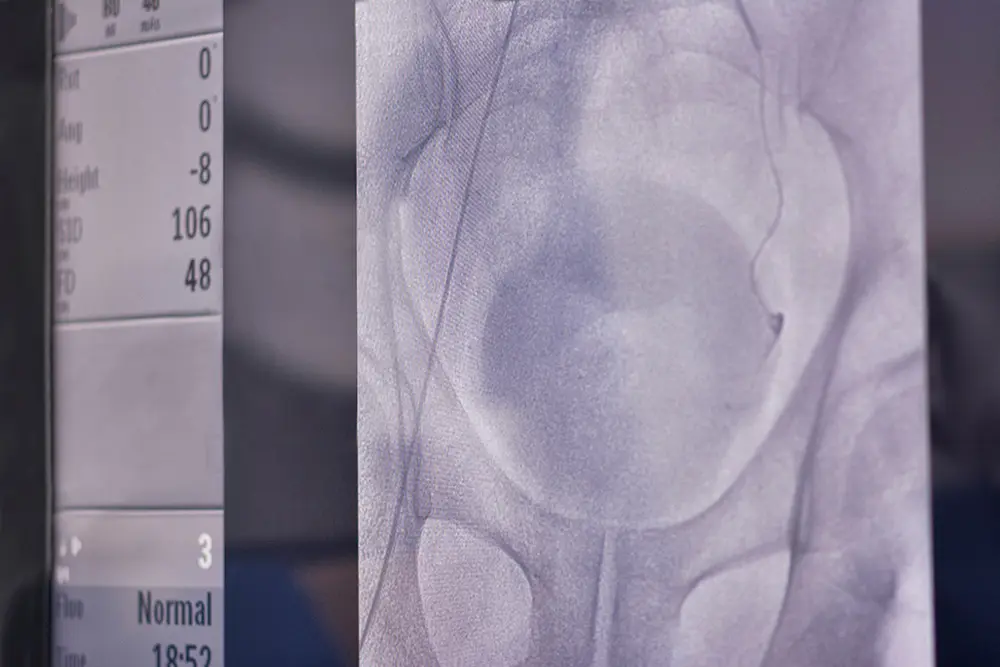

Close-up of a medical X-ray image showing a hip joint and pelvis area, with part of a monitor displaying numeric data and measurements visible on the left side.

As the procedure begins, a small incision will be made in your upper thigh or wrist as to gain access to your arterial system. A small, spaghetti-like catheter is then placed into the vessels that supply blood to your prostate.

As the prostate is reached, small microscopic particles are injected into the blood vessels and the blood flow to your prostate is decreased. This process will be repeated as to reach both sides of the prostate.